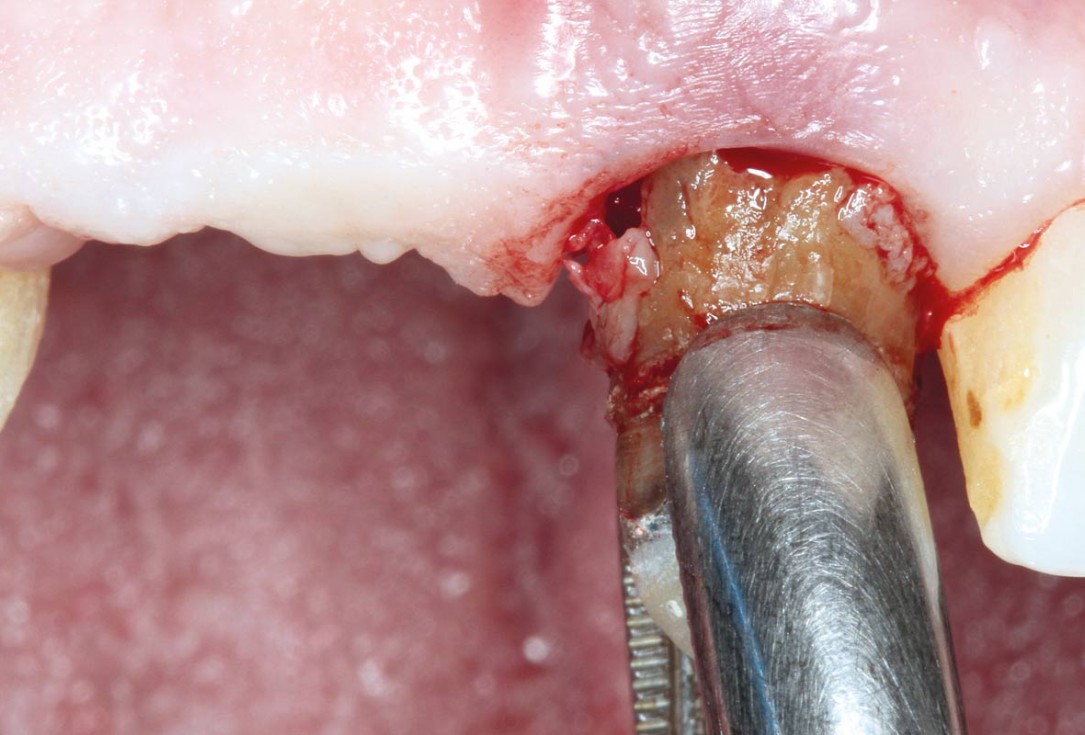

03/17 - Extraction of tooth 21.

Socket preservation using cerabone® and Straumann® Emdogain® - Dr. S. Pelekanos